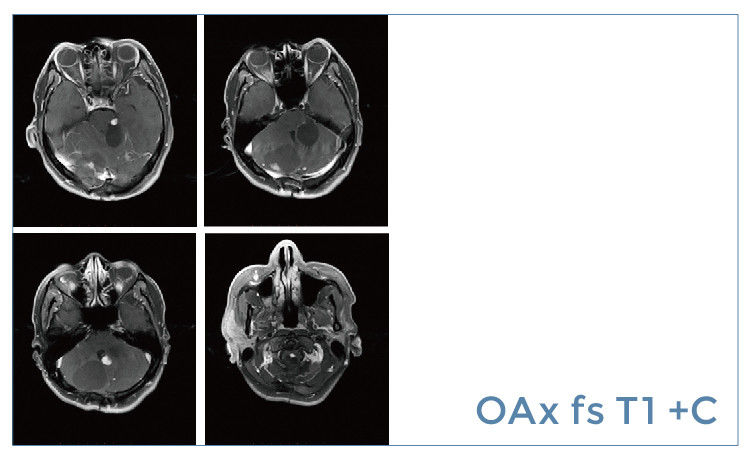

【朗润影像档案】磁共振影像病例分享(编号20190614)